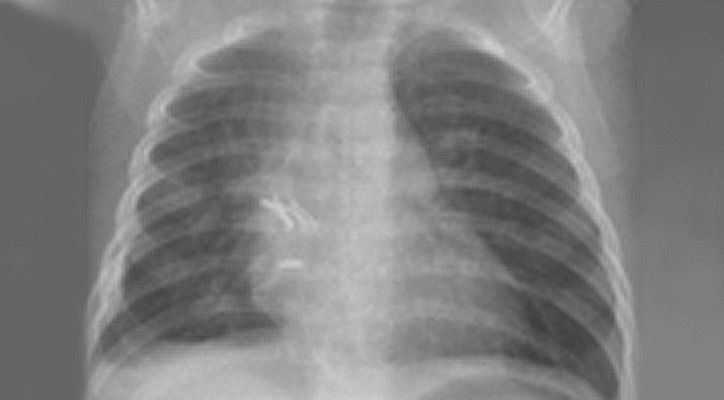

Zwerchfellhernien sind angeborene Defekte des Zwerchfells. Diese werden bei den meisten Kindern vor Geburt im Ultraschall erkannt. Je nach Lokalisation und Ausprägung verursachen sie teilweise erhebliche Probleme mit der Atmung für das Neugeborene. Deshalb sollten alle Schwangeren bei deren Kindern diese Fehlbildung festgestellt wird eng an ein Zentrum wie Tübingen angebunden werden und das Kind dort zur Welt bringen. bereits vor Geburt  Bereits in der Diagnostik vor Geburt mit Ultraschall und Kernspintomographie lässt sich das Risiko für die Beeinträchtigung der Atmung anhand der Lungengröße abschätzen. Damit ist gewährleistet, dass die Geburtshelfer, die Neonatologen und Kinderintensivmediziner darauf vorbereitet sind und alle Therapiemöglichkeiten direkt zur Verfügung stehen. Dies umfasst am Universitätsklinikum Tübingen alle modernen Therapieoptionen beginnend von Eingriffen im Mutterleib, über eine direkte Versorgung des Neugeborenen solange es noch durch die Nabelschnur versorgt wird bis hin zu speziellen Beatmungsformen nach Geburt und der Sauerstoffzufuhr über das Blut (ECMO). Als überregionales Zentrum für Fehlbildungen beim Neugeborenen sind alle diese Therapieformen bei uns mit jahrelanger Erfahrung etabliert.

Nach Geburt wird das Kind zunächst über mehrere Tage hinweg intensivmedizinisch stabilisiert, bis eine Operation möglich ist. Nach entsprechender Patientenselektion wird die Korrektur minimalinvasiv oder offen chirurgisch durchgeführt.